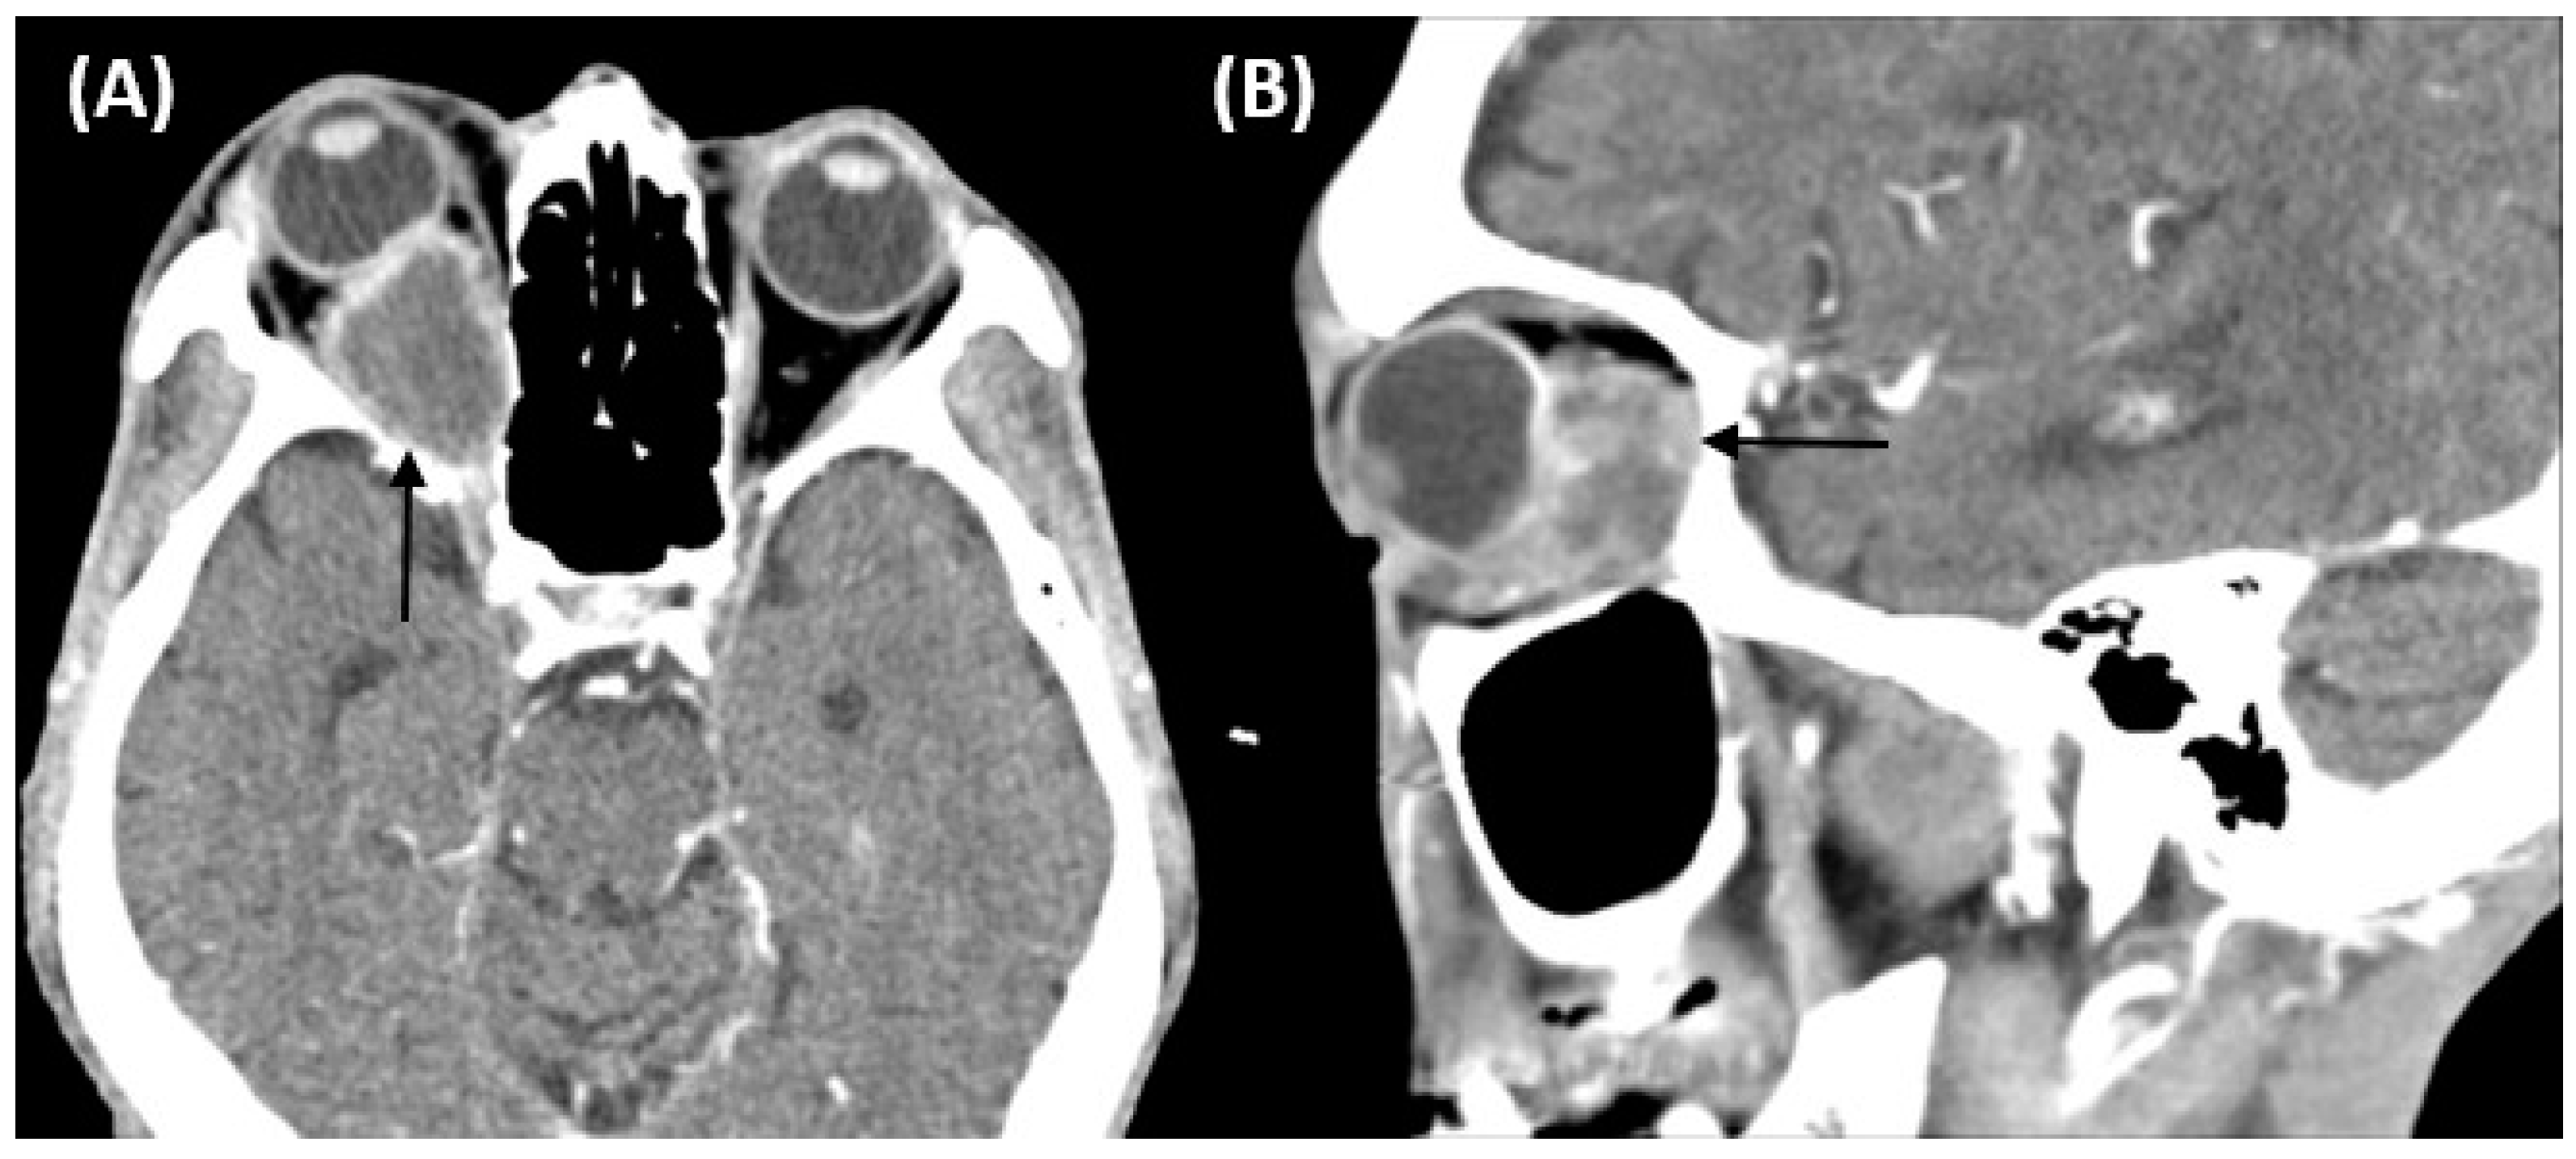

Rare Orbital Metastasis Originating from Ampullary Adenocarcinoma

2. Case Report